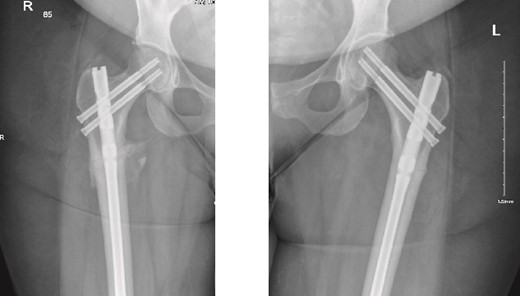

The patient was seen in the clinic at 2 weeks, 6 weeks, and 6 months post-surgery. She was doing well, reporting only mild pain. She was fully weight-bearing with the assistance of a cane and had good range of motion (Figs 3 and 4).

6-weeks follow-up anteroposterior (AP) view of the right and left femurs after CRIF with IM nail.

6-months follow-up anteroposterior (AP) view of the right and left femurs after CRIF with IM nail.